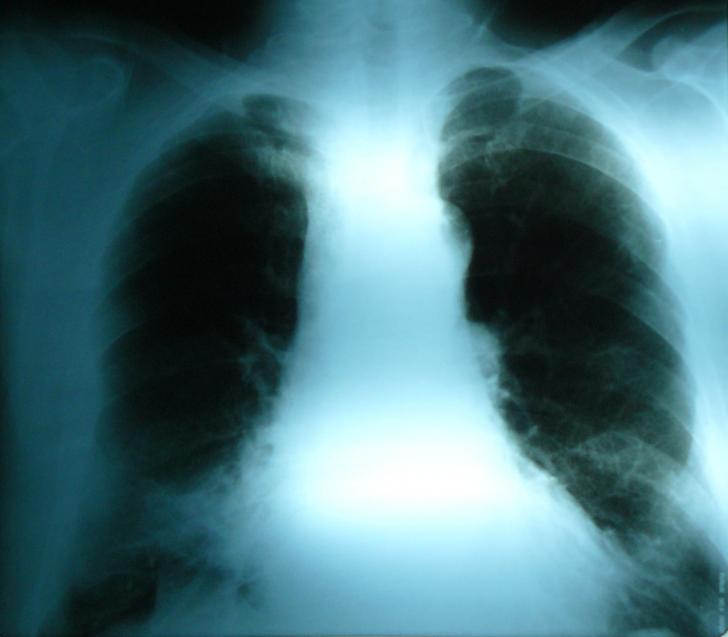

ANEVRISM SACCIFORM DE CROSA AORTICA LA UN PACIENT ASIMPTOMATIC SI PROBLEMELE DE CONDUITA TERAPEUTICA

ANEVRISM SACCIFORM DE CROSA AORTICA LA UN PACIENT ASIMPTOMATIC SI PROBLEMELE DE CONDUITA TERAPEUTICA Definitie: Anevrismul de aorta reprezinta dilatarea aortei de peste 1,5 ori diametrul aortei corespunzator segmentului respectCiteste tot ... 1147 cuvinte

Dimensiune mica + cu imagini |